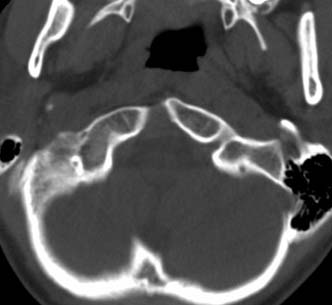

标题: PED0678:男,10岁,寰枢椎平扫。

患者在校与同龄孩子打闹后(据家长说被拳击中颈部)出现颈部不适30分钟后入院检查,来时脖子歪斜。请大家看看枢椎齿状突及寰枢关节有问题吗?(3mm层厚断层扫描)。